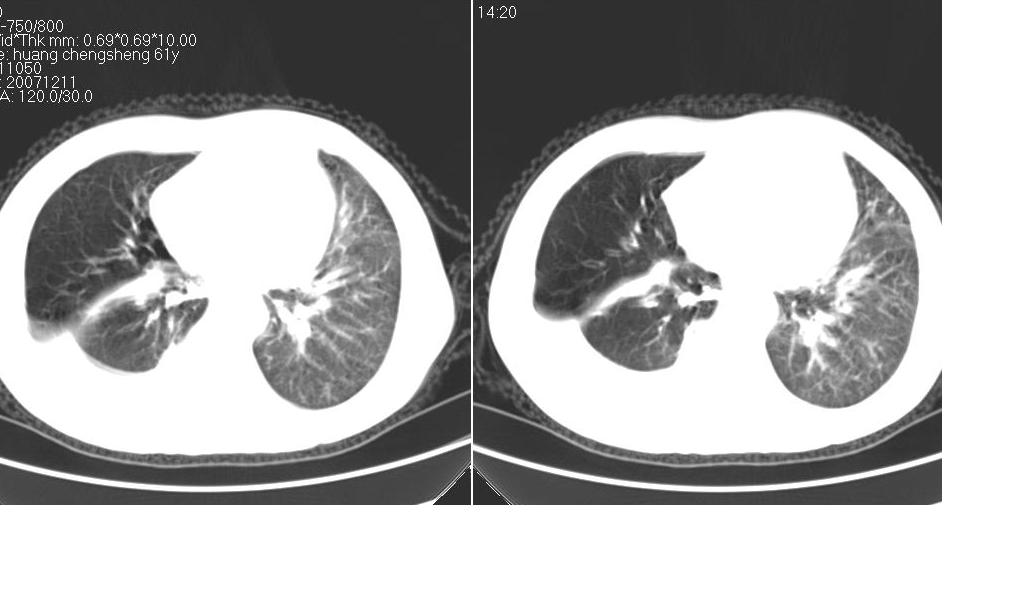

男 61岁,已确诊肺癌半年余.

考虑:1、右肺下叶中心型肺癌并纵隔淋巴结转移。胸腔积液。

2、心包少量积液。

3、左肺改变不除外癌性淋巴管炎或化疗后肺间质纤维化。

1 右肺下叶中心型肺癌.纵隔内淋巴结转移.右侧胸腔积液. 2 心包少量积液.3 肺间性改变考虑与化疗有关.

补充一下:右肺底好象有一个类圆形的结节影,可考虑为肺部转移。如图示。[

考虑:1、右肺下叶中心型肺癌并纵隔及左肺门淋巴结转移。胸腔积液。

3、左肺改变与左肺门肿大淋巴结影压迫主支气管有关。